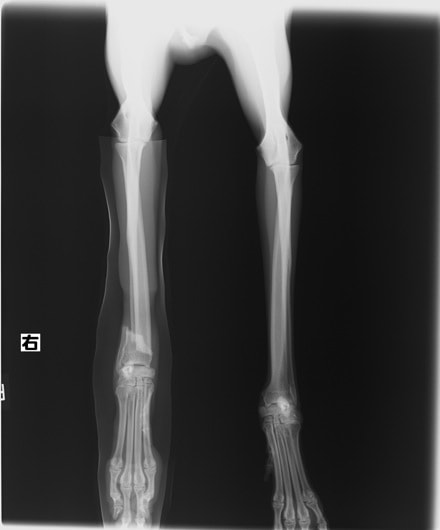

症例3:キルシュナーワイヤーのピンニングによる整復

ペルシャ猫 11ヶ月齢 雄

他院にて左大腿骨遠位の成長板骨折(salter-harrisⅠ型)が認められており、治療相談を目的として来院。当院にて、キルシュナーワイヤーを用いたピンニングにより骨折部位の整復を行いました。術後の経過は良好で、現在も経過観察中です。

術前レントゲン

術後レントゲン